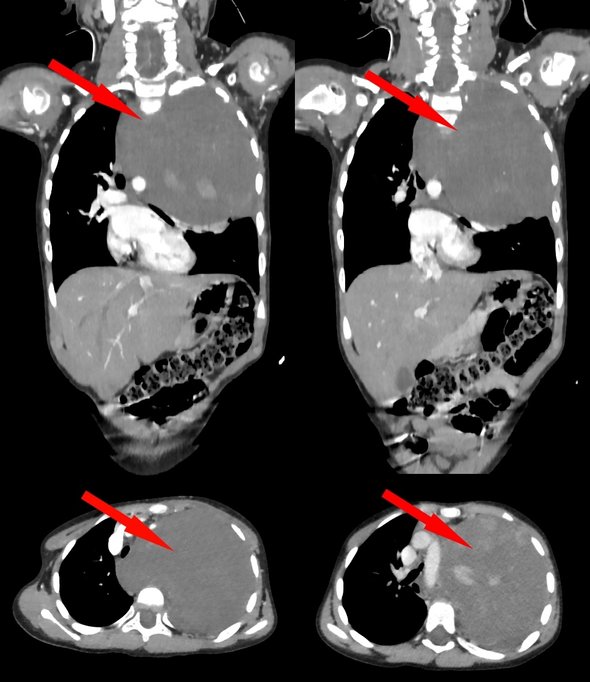

КТ, проведенное в клинике по месту жительства, показало крупное образование, после чего девочку направили в РДКБ. Дополнительные обследования установилии, что через плотную ткань опухоли проходили позвоночная и подключичная артерии. Результаты биопсии показали, что опухоль размером 10×12 см занимает 75% плевральной полости, имеет доброкачественную природу, но смещает аорту и сдавливает сердце с легким.

Однако врачи все же решили удалить образование единым блоком, поскольку оно могло содержать злокачественные клетки. «Учитывая гигантский размер опухоли и ее расположение вблизи множества жизненно важных структур, мы использовали расширенный доступ по типу „раковины моллюска“. Он предполагает рассечение не только межреберного промежутка, но и самой грудины, что позволяет „раскрыть“ грудную клетку. Только так мы смогли получить полный визуальный и инструментальный контроль над аортой и всеми сосудами», — рассказал завотделением реконструктивной хирургии РДКБ Евгений Андреев.